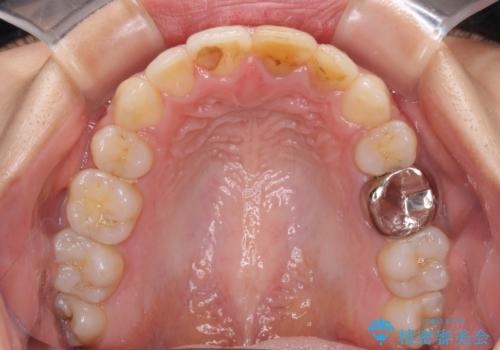

八重歯の抜歯矯正 費用を抑えた矯正装置

- 上の八重歯を気にして来院された患者様です。

受け口傾向にあるため、上顎前歯の叢生解消とともに下顎前歯を後方へ移動させることを目的とし、上下左右の第一小臼歯4歯を抜歯することとしました。

受け口傾向の方の下顎抜歯矯正では、下顎前歯の歯肉が退縮することがあります。前歯を移動させるときには、歯肉退縮が起こらないように工夫する必要があります。